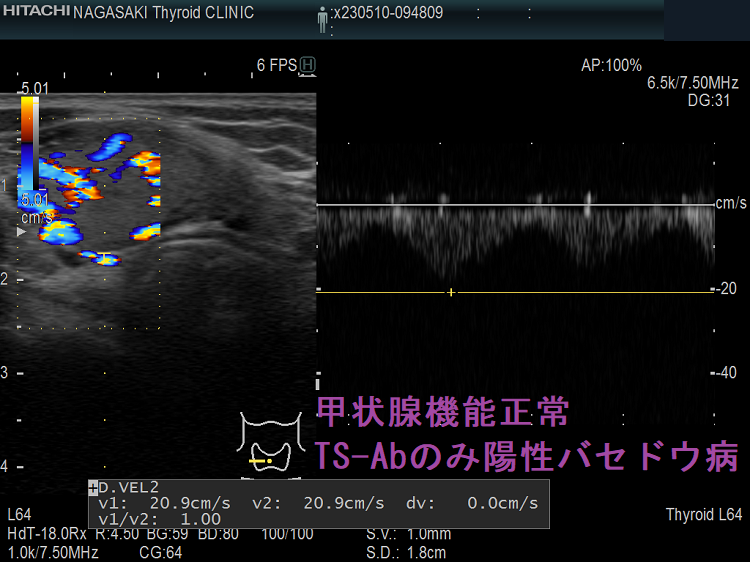

甲状腺機能正常、TSAbのみ陽性バセドウ病 超音波(エコー)画像 下甲状腺動脈血流速度(ITA-PSV)は正常

TSAb 3000%台 甲状腺機能正常バセドウ病 下甲状腺動脈血流速度(ITA-PSV)は正常